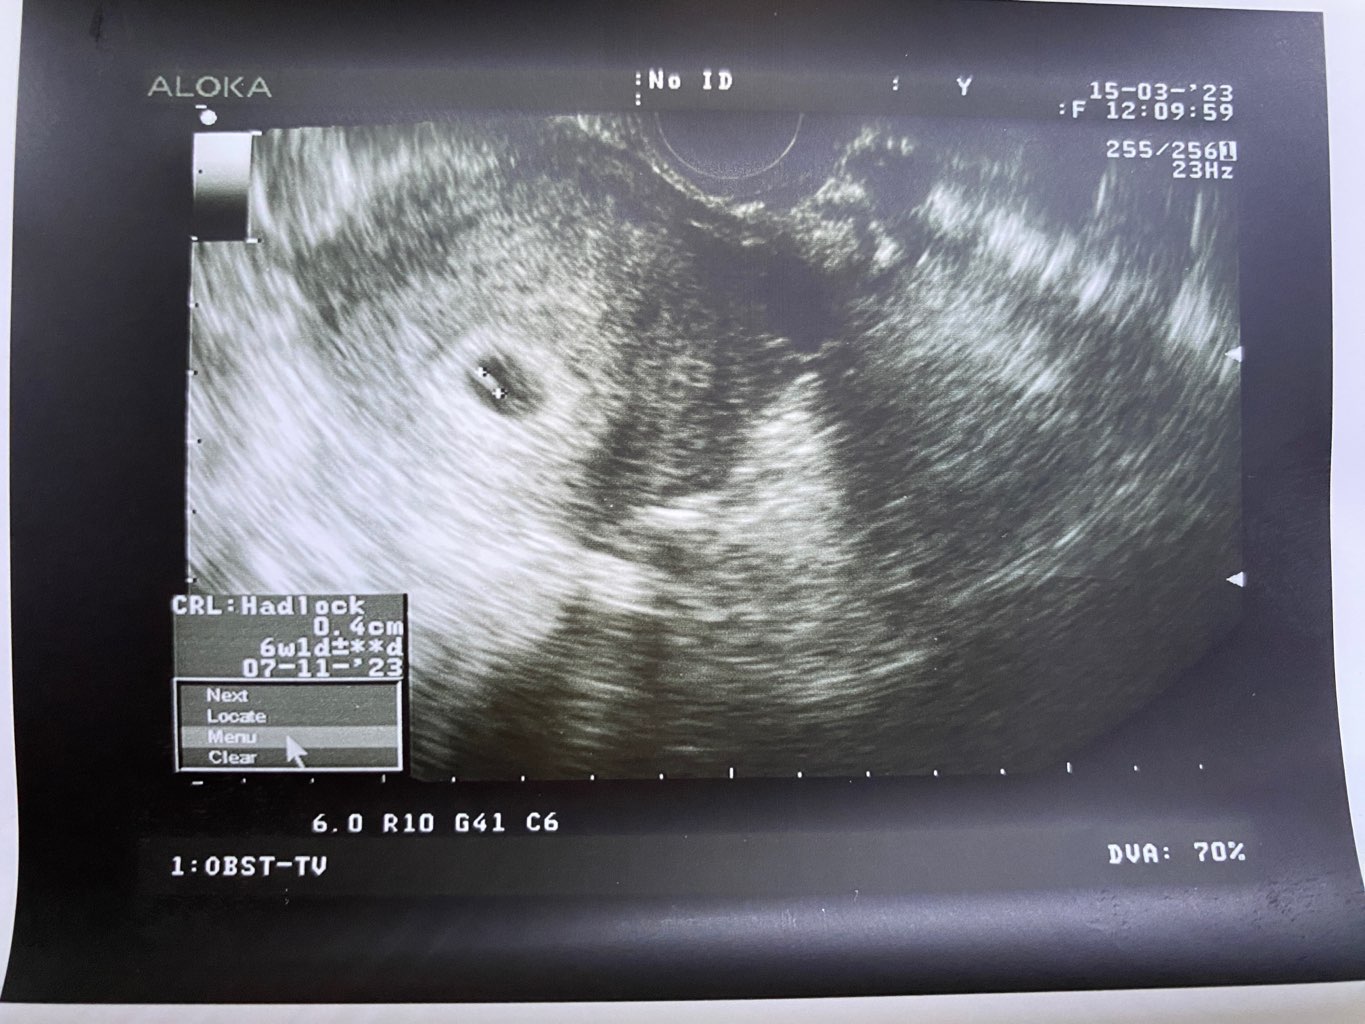

Cudownie Kochana!Dziewczyny jest serduszko, jest i bije

6+1 wiec proszę o przepisanie mnie na 8 listopada. Nie watpcie w swoje kropeczki tak jak ja, nie wolno ! Ja już nie zwątpię nigdy i Wam tez zabraniam![]()

Cudowna wiadomość!!Dziewczyny jest serduszko, jest i bije

No i to jest piękna wiadomośćDziewczyny jest serduszko, jest i bije